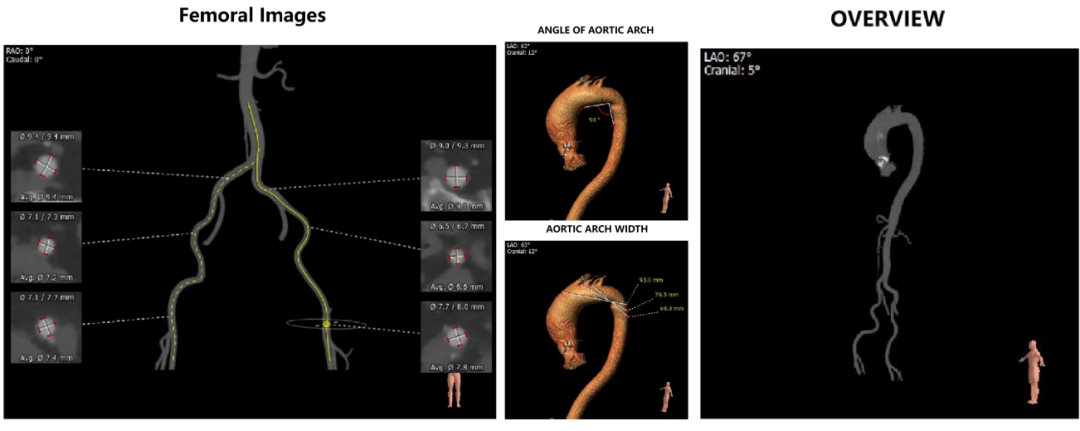

左冠开口高度15.0mm,右冠开口高度15.0mm,双侧冠脉预估术后灌注良好;左室腔较小,心室壁可见明显增厚。

外周血管及主动脉弓解剖:

入路血管无严重钙化及其他病变,双侧血管内径良好,整体入路血管条件良好。